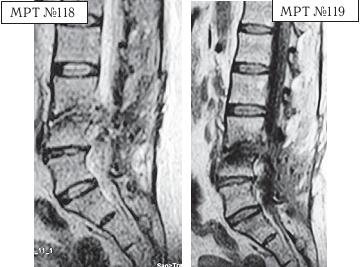

На МРТ,№ 118 (в режиме Т2-ВИ) и № 119 (в режиме Т1-ВИ) той же пациентки наблюдается состояние после двух операций.

На МРТ№ 119 в режиме Т1-ВИ отчётливо видно (по следу), что хирург пытался исправить свою предыдущую ошибку и прооперировал на этот раз протрузию межпозвонкового диска в сегменте LIV-LV Также наблюдаются последствия спондилодисцита, образовавшегося после операций, вследствие развития которого произошла деструкция замыкательных пластин в сегменте LIII—LIV и деформация тела LIV позвонка. А также произошло послеоперационное образование грыжи межпозвонкового диска в сегменте LIII-LIV. На данных снимках наблюдается выраженный рубцовоспаечный процесс на уровне прооперированных сегментов, который опутал своими тяжами дуральный мешок и спинномозговые корешки, чем, собственно, и объясняется столь тяжёлое состояние данной пациентки.